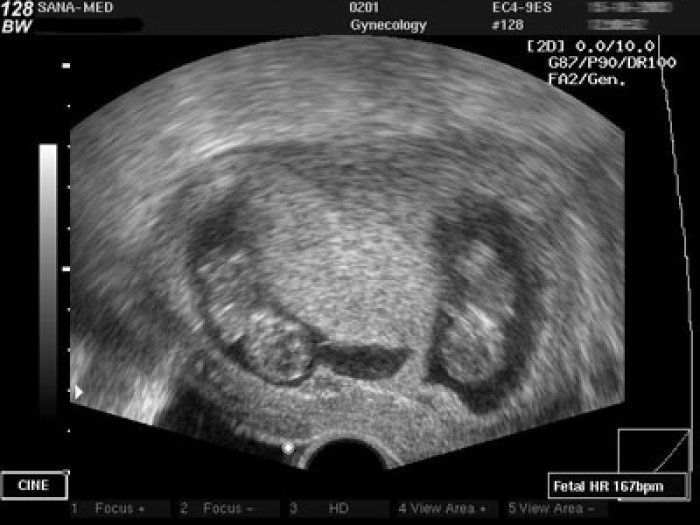

Если беременность многоплодная, то для плода существуют свои нормы КТР. В целом, при наличии двойни или тройни эмбрионы будут меньше, чем если в матке развивается одноплодная беременность. Основные факторы, ограничивающие рост — дефицит внутриматочного пространства и питания, поступающего по сосудам плаценты.

При многоплодной беременности значения КТР плодов отличаются

КТР плода при одноплодной и многоплодной беременности — сравнительная таблица

| Срок беременности в неделях |

КТР плода при многоплодной беременности, мм |

КТР плода при одноплодной беременности, мм |

| 8 недель | 15 | 16 |

| 9 недель | 21 | 23 |

| 10 недель | 29 | 31 |

| 11 недель | 39 | 41 |

| 12 недель | 53 | 54 |

| 13 недель | 72 | 74 |

| 14 недель | 84 | 87 |